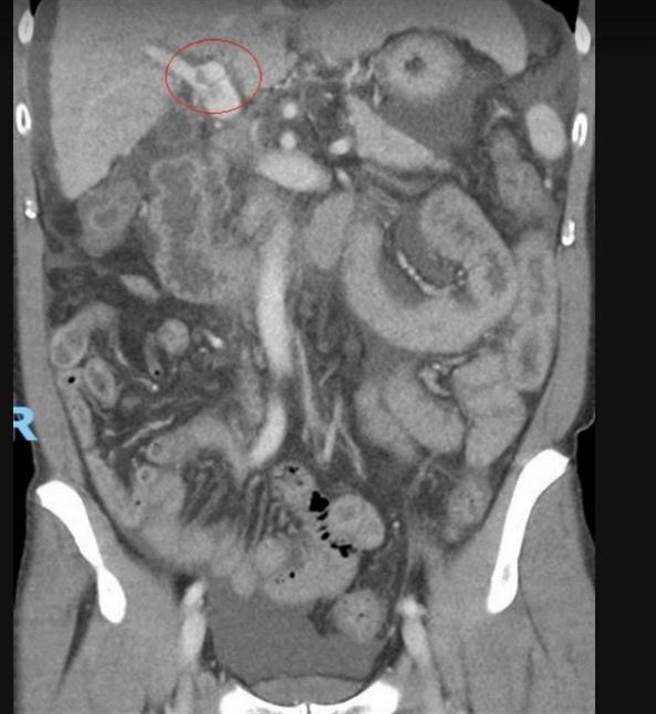

53岁的詹姓男子轻忽B肝,10多年未追踪竟已是晚期肝癌,肿瘤10公分,经治疗后,肿瘤几乎都消失了。(彰化医院提供/吴敏菁彰化传真)

宋时雨劝他不要放弃希望,建议先处理肝门静脉的肿瘤,透过精准定位的呼吸调控放射线治疗及口服标靶药物,先将癌细胞消灭,届时就可以进入肝臟移植或肿瘤栓塞治疗。经过1个多月15次放疗之后,詹先生的肝门静脉肿瘤几乎消失了,也顺利地进入外科手术评估,重燃希望。